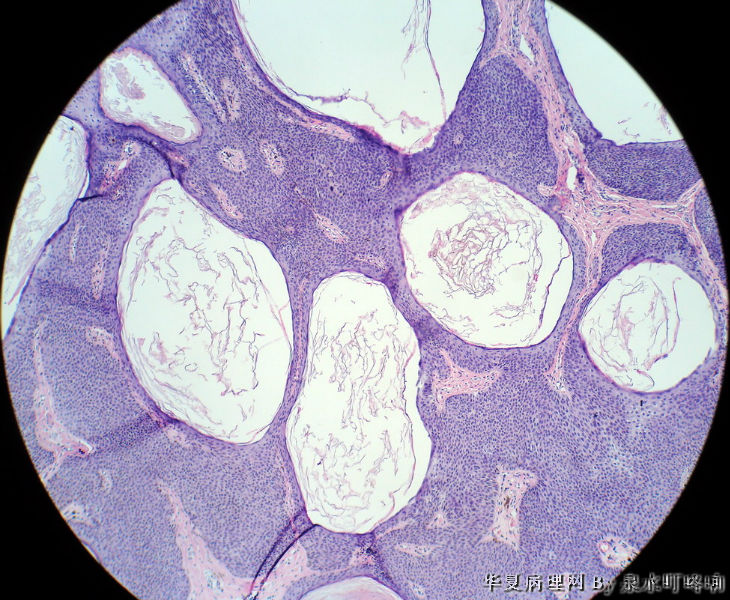

男,80岁,左耳后肿物十余年。

参考诊断

棘层肥厚型脂溢性角化症